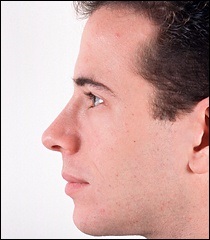

A fénykép a bal oldalon mutatja egy ember tipikus megnövekedett nazális gerinc. Ez jelentősen növeli az orrát előre. A fénykép után a művelet ugyanaz az ember nagyon jól néz ki.